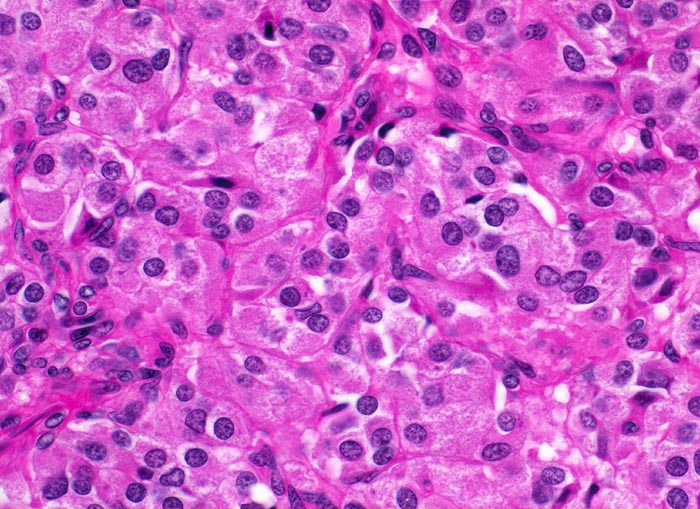

medulläres Schilddrüsenkarzinom

Die polygonalen Tumorzellen bilden Zellballen, welche von schmalen Bindegewebssepten umsponnen werden. Die Tumorzellen haben reichlich feingranuläres Zytoplasma und runde Kerne mit feinkörnigem Chromatin.

Mehrere scharf begrenzte weisse Knoten in beiden Schilddrüsenlappen von bis zu 8mm Durchmesser.

Beim Vater der Patientin wurde ein bilaterales Phäochromozytom diagnostiziert und in der Folge eine multiple endokrine Neoplasie vom Typ 2A. Im Familienscreening wurde bei der Patientin eine Mutation im Ret-Protoonkogen nachgewiesen und eine prophylaktische Thyreoidektomie durchgeführt.